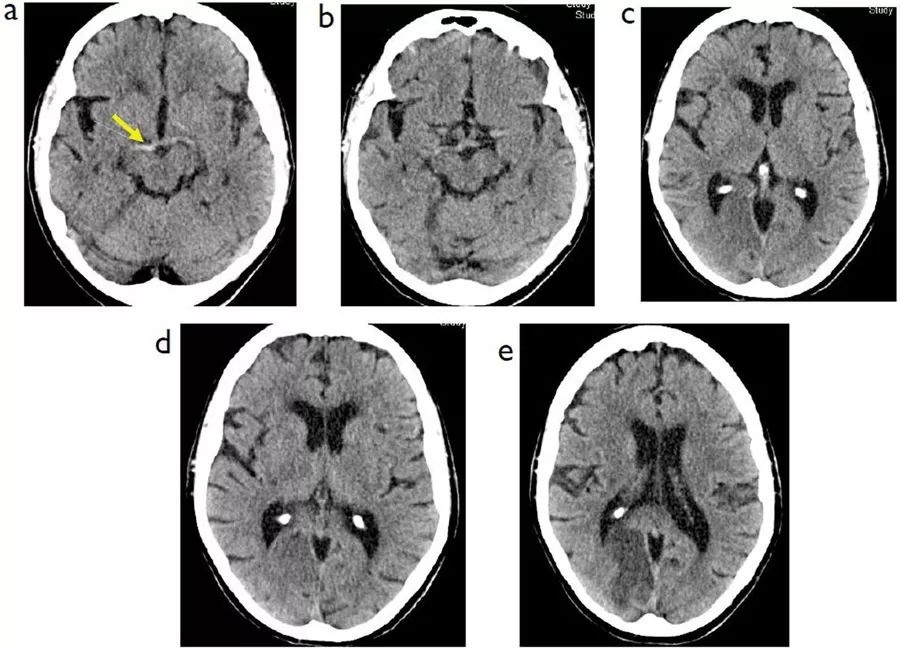

例3

图3  65岁女性,突发左侧无力、左侧同向偏盲,A:就诊时CT;B~D:36小时后CT;E:5天后CT

本例患者为右侧大脑后动脉的高密度征。在最初就诊时,患者的脑实质显得很正常,而在36小时后,患者右侧枕叶和右前丘脑出现密度降低。5天后,患者脑内的梗死灶演变成了明显的低密度,边界较清晰。